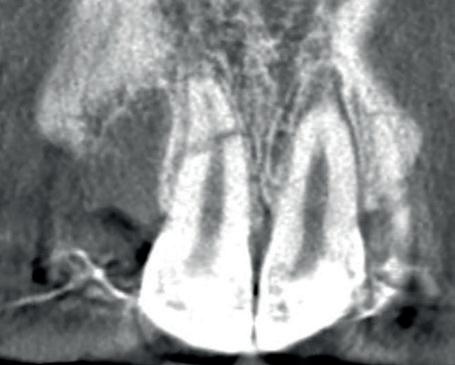

Voordat je aan een wortelkanaalbehandeling begint, zorg je voor (of maak je) een goede beginfoto waar het te behandelen gebitselement volledig op staat afgebeeld. Deze foto geeft essentiële informatie: de grootte van de pulpakamer en de ligging ervan; het aantal en de vorm van de wortels en de breedte van hun wortelkanalen en de lengte van de wortels. Hiermee kan je de DETI-score bepalen en de moeilijkheidsgraad inschatten. De grootte en de ligging van de pulpakamer op de röntgenfoto in combinatie met de ideale anatomische vorm, zoals in foto 1 is aangegeven, bepaalt de uiteindelijke vormgeving van de opening. Bij de molaren liggen de kanaalingangen in de buurt van de knobbeltoppen. Als die niet meer in originele staat

1. De locatie van de kanaalingangen ten opzichte van de occlusale morfologie (rood). In zwart is de ideale of standaard opening ingetekend. De uiteindelijke vorm van de opening is voorts ook afhankelijk van de klinische situatie, die vooral vanuit een goede begin foto wordt verkregen.